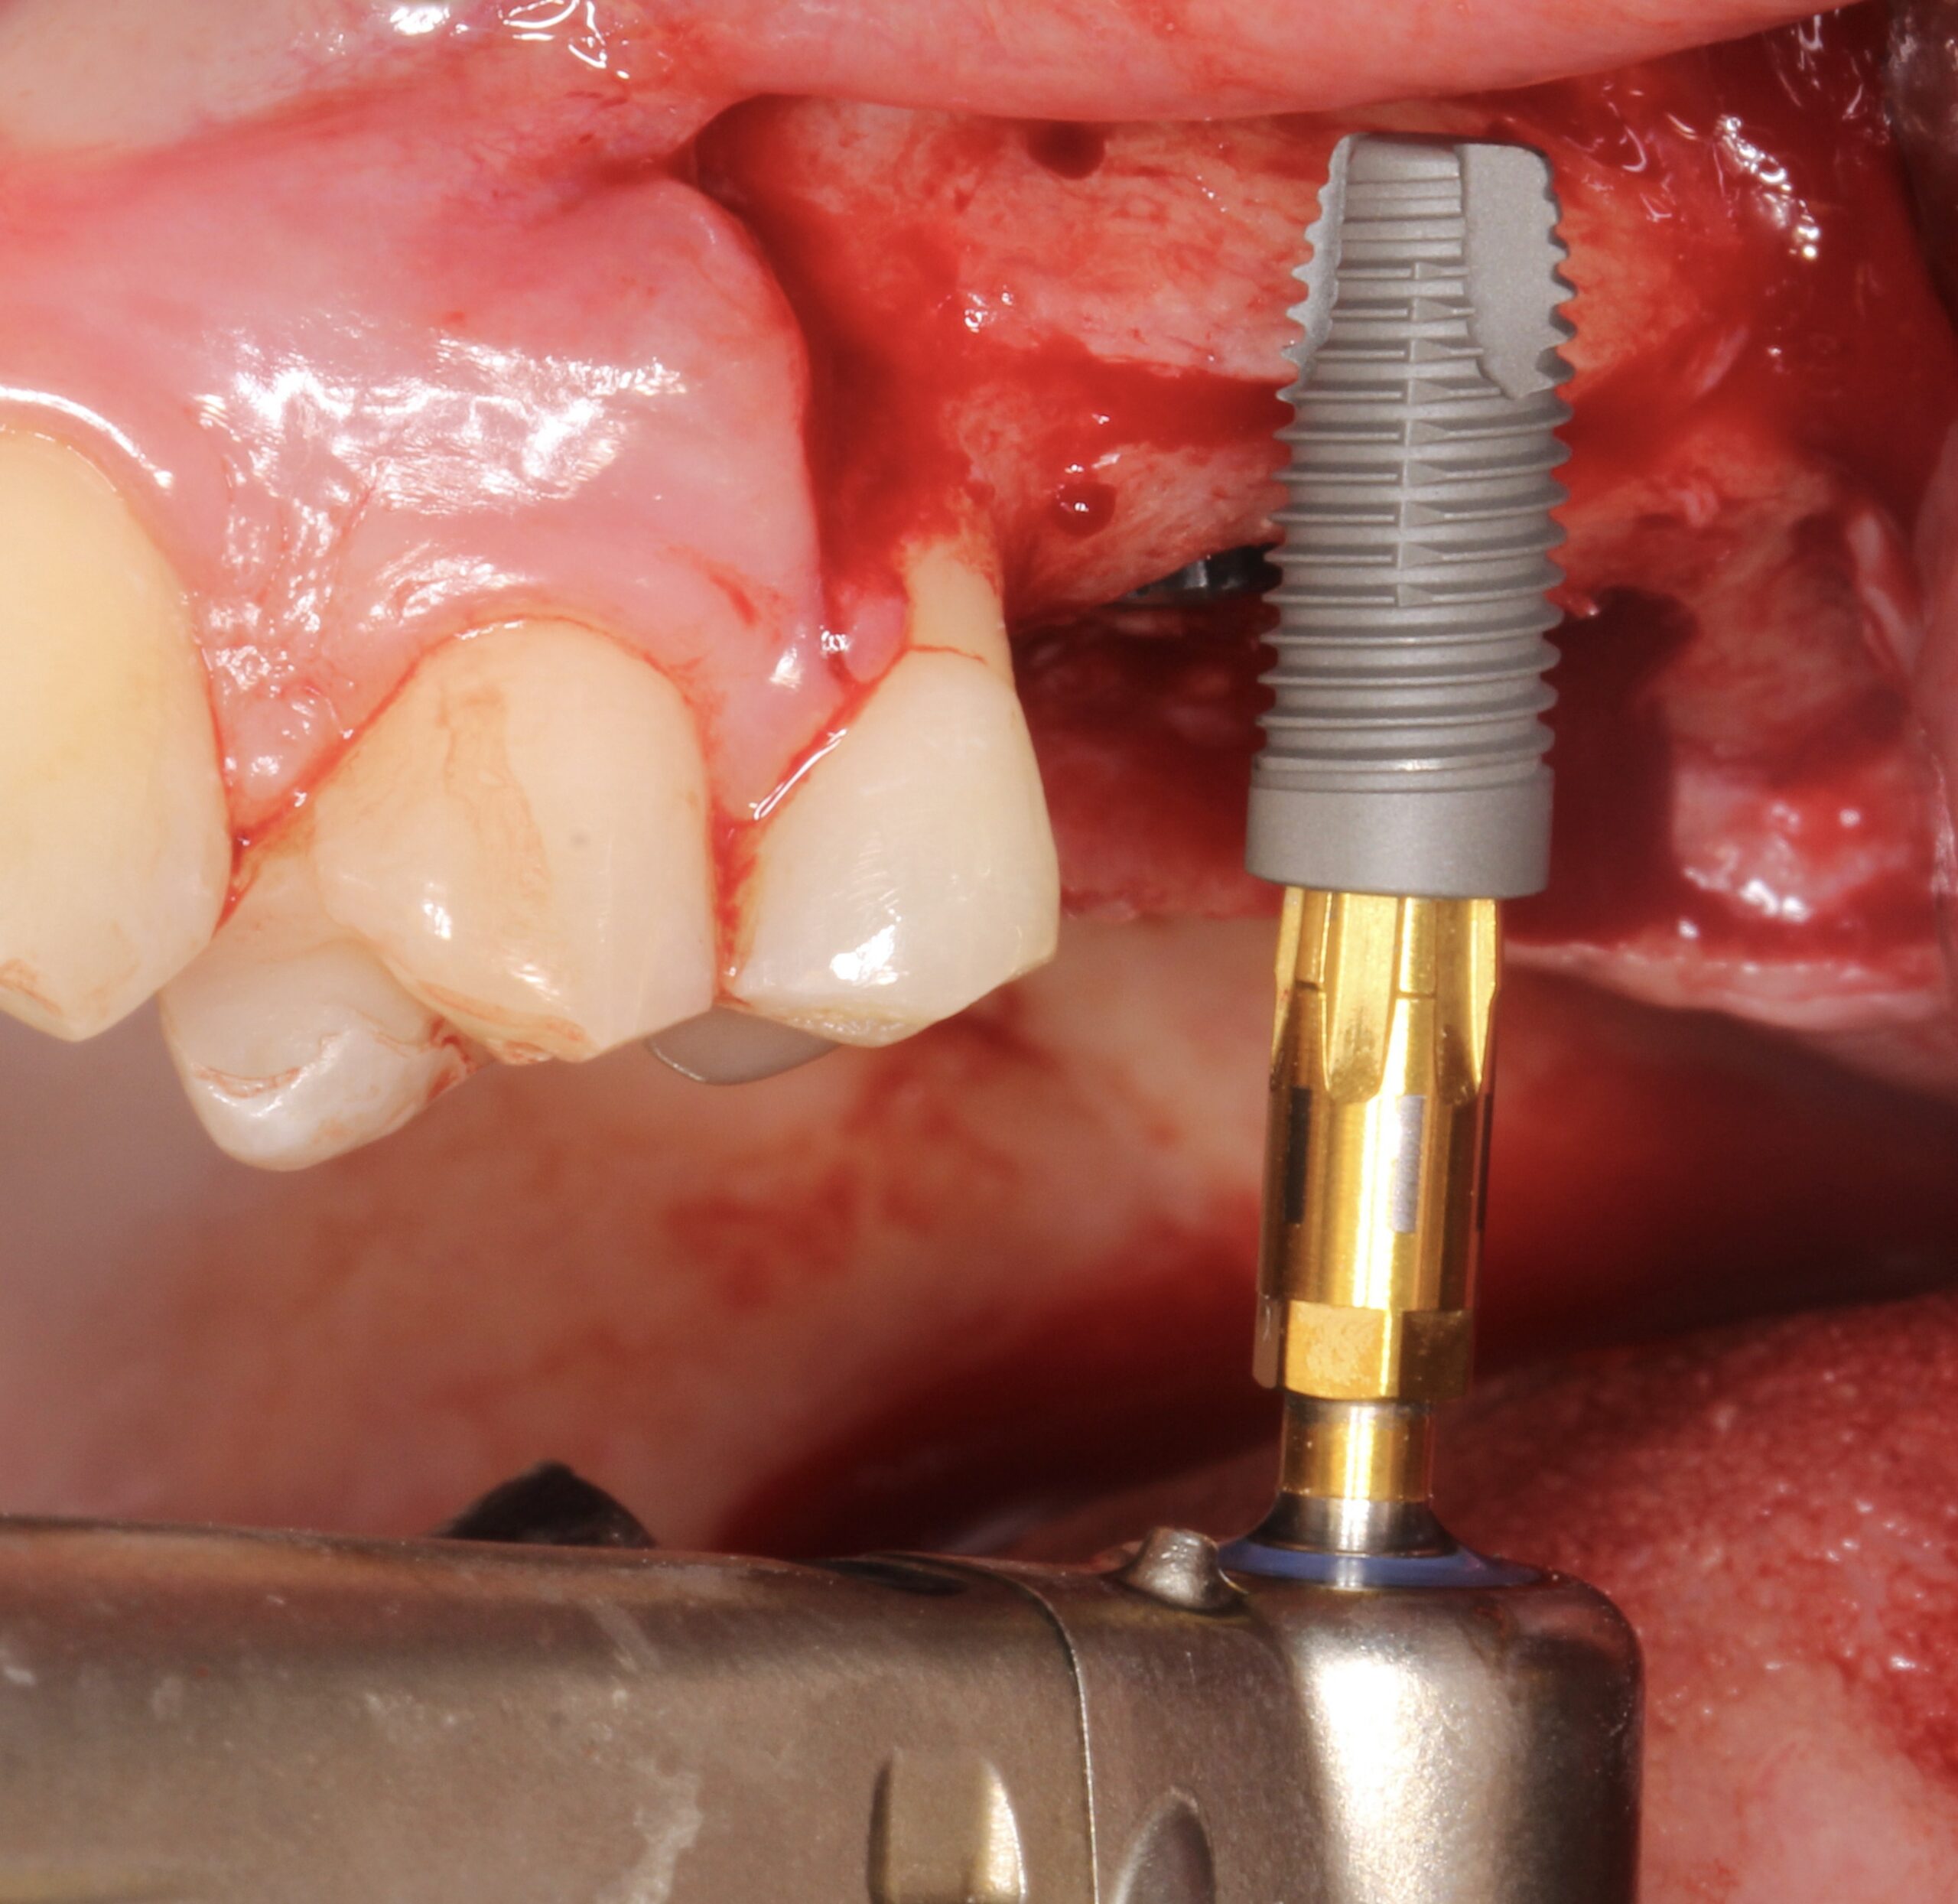

Figure 13.

2 Neoss ProActive® Straight implants (4.5 x 11 mm) were placed.

Figure 14.

Occlusal view of the implants.